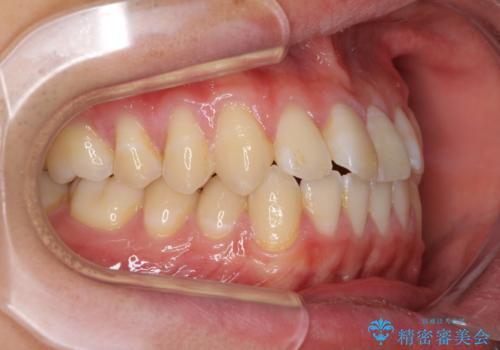

- 上下前歯のデコボコを気にして来院された患者様です。

叢生は軽微であり、費用を抑えて期間もあまりかけずに治療をしたいとのことで、インビザライン・ライトを用いて矯正治療を行うこととしました。

途中通院できなくなり、マウスピースの装着もしっかりとできなかったため、治療期間が長くかかってしまいました。